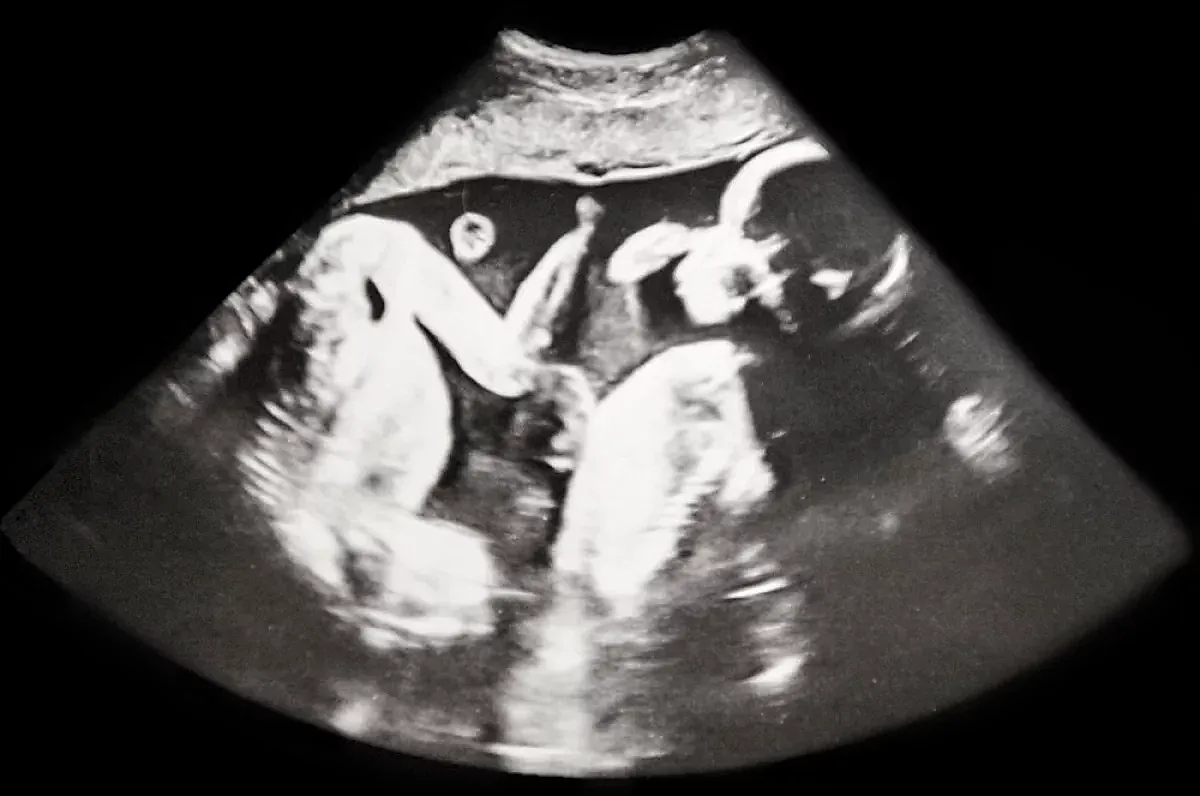

Недавно жительница Петербурга стала героиней одной из самых удивительных новостей в области репродуктивной медицины: у неё родились сразу четыре девочки-близнеца, и все они — однояйцевые близнецы. Этот уникальный случай стал первым в истории российской практики и вызывает искренний интерес специалистов всего мира. Девочки появились на свет на 32-й неделе беременности, что считается чуть раньше стандартного срока, однако при такой сложной многоплодной беременности это вполне благополучный результат. Вес малышей варьировал от 1360 до 1640 граммов, а их рост — от 37 до 41 сантиметра.

Что же такое однояйцевые близнецы и почему их появление так редко? В медицинской практике считается очень деликатой темой. Они возникают в результате деления одной оплодотворённой яйцеклетки — зиготы — на несколько эмбрионов. Для двойни это деление происходит один раз, а для тройни или четверни — как минимум два раза. Главное отличие в том, что при делении происходит примерно на 4–8-й день после оплодотворения, и в результате формируется одна плацента и одна амниотическая оболочка (монохориальная структура). Именно такой случай и стал причиной появления четырех идентичных девочек.